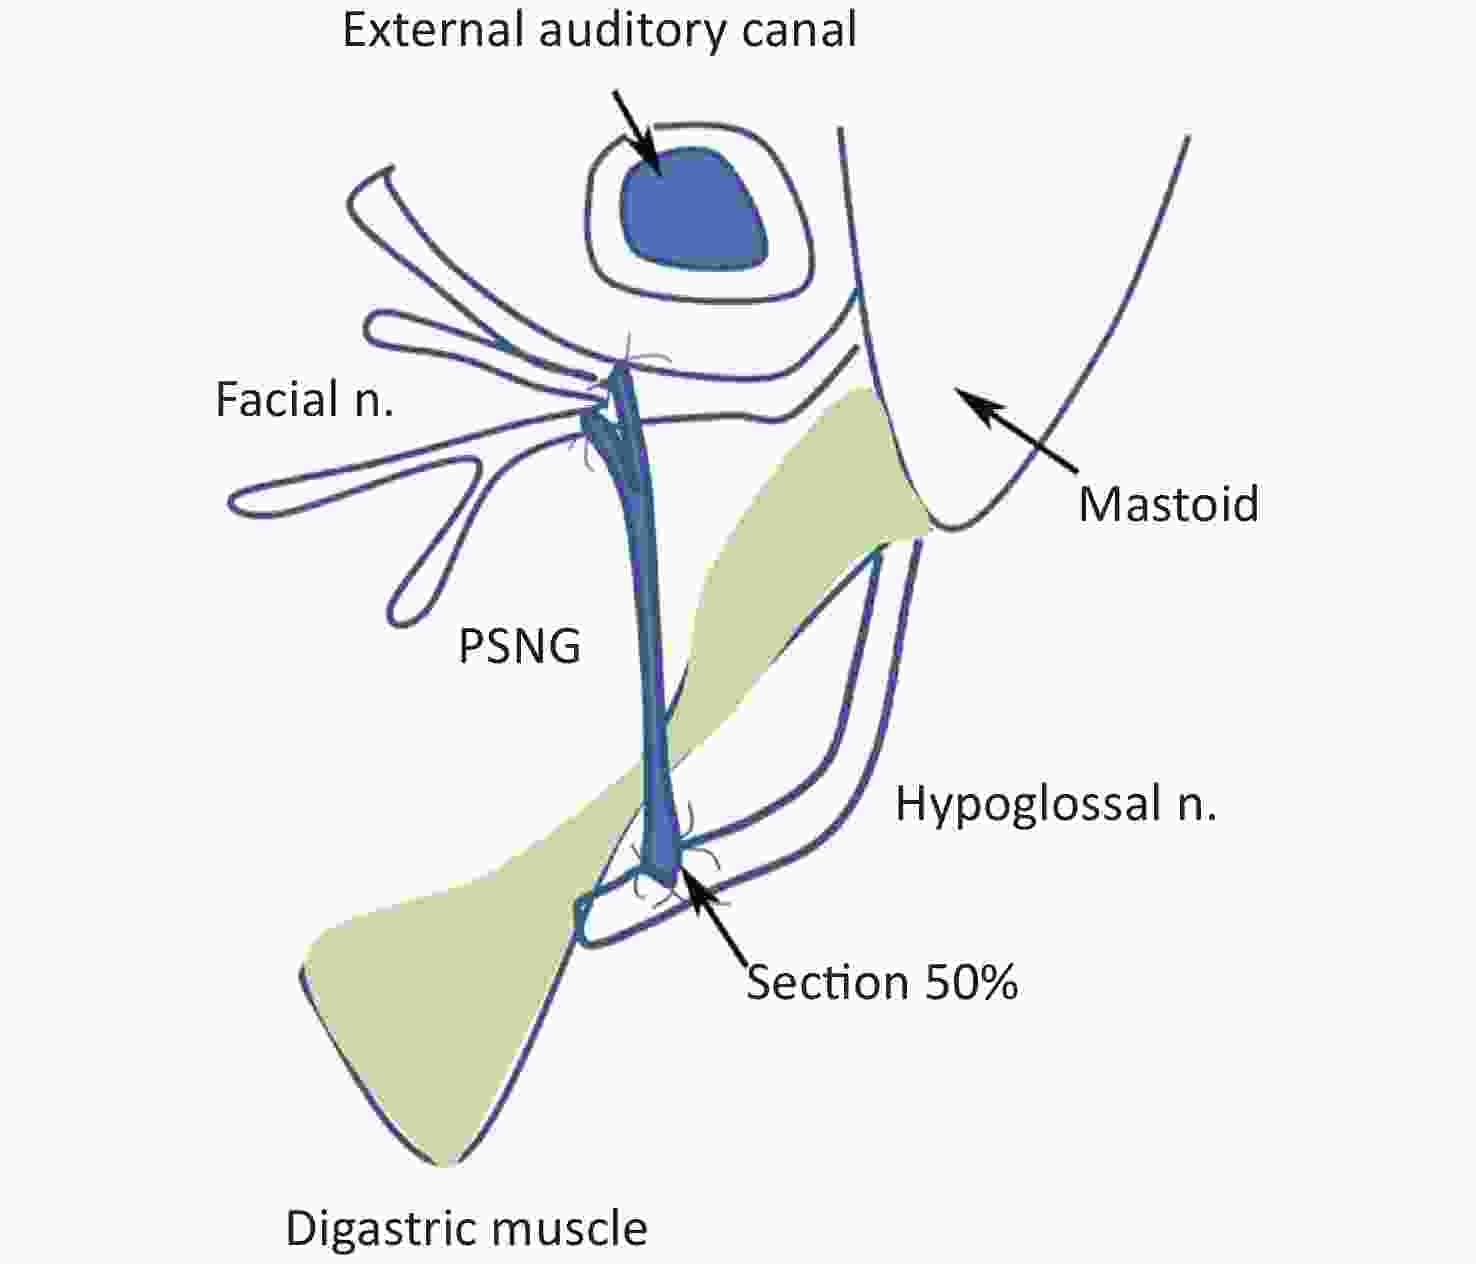

Figure 3 from Hypoglossal-facial-jump-anastomosis without an …

Hypoglossal Facial Anastomosis | Ento Key